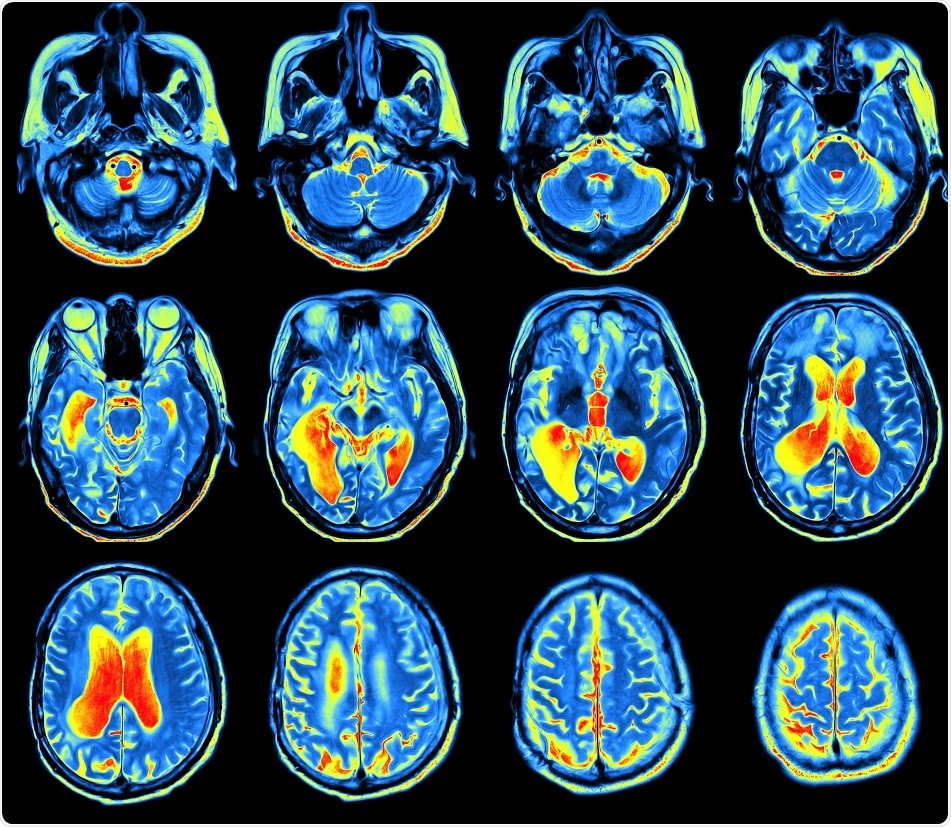

Credit: MriMan/ Shutterstock.com

The study, which was published in the journal Neuron, suggests that it is possible to build up a map of the connectome---the connections in the brain---by examining conventional brain scans obtained using a magnetic resonance imaging (MRI) scanner.

A conventional MRI scan provides a single image of the brain that enables the calculation of multiple structural features of the brain; i. e., each region of the brain can be described using nearly ten distinct characteristics.